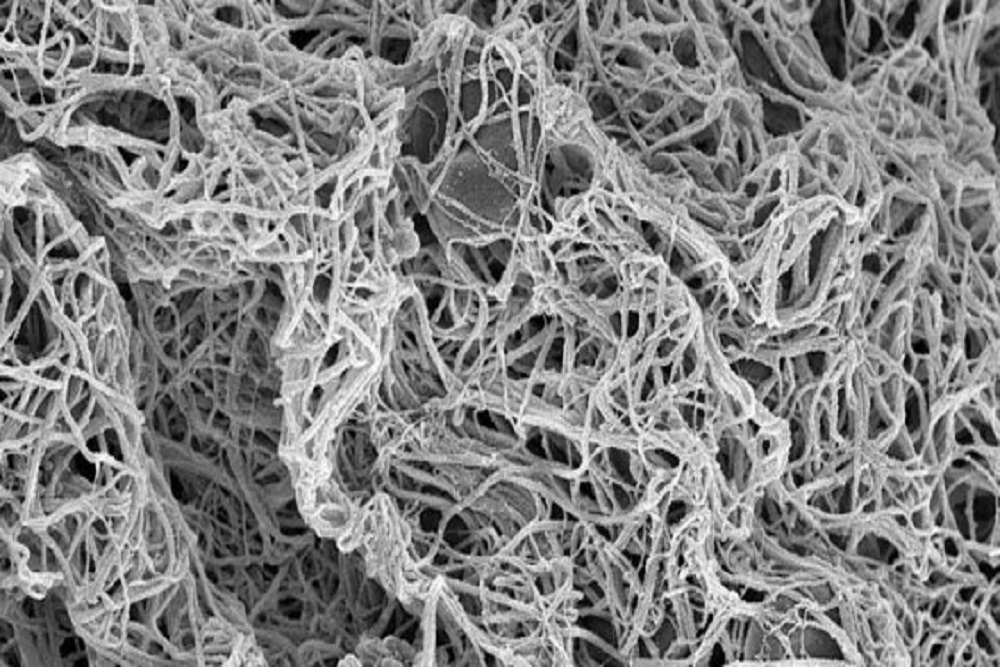

Research links gut fungi to intestinal inflammation in Crohn’s disease patients

Results of a new study by researchers at Case Western Reserve University represent a step toward improving our understanding of Crohn’s disease and the factors that cause its intestinal inflammation.

Stopping heavy bleeding with next-generation artificial platelets

Case Western Reserve University researchers develop next generation of artificial platelets that can stop bleeding from an injury faster